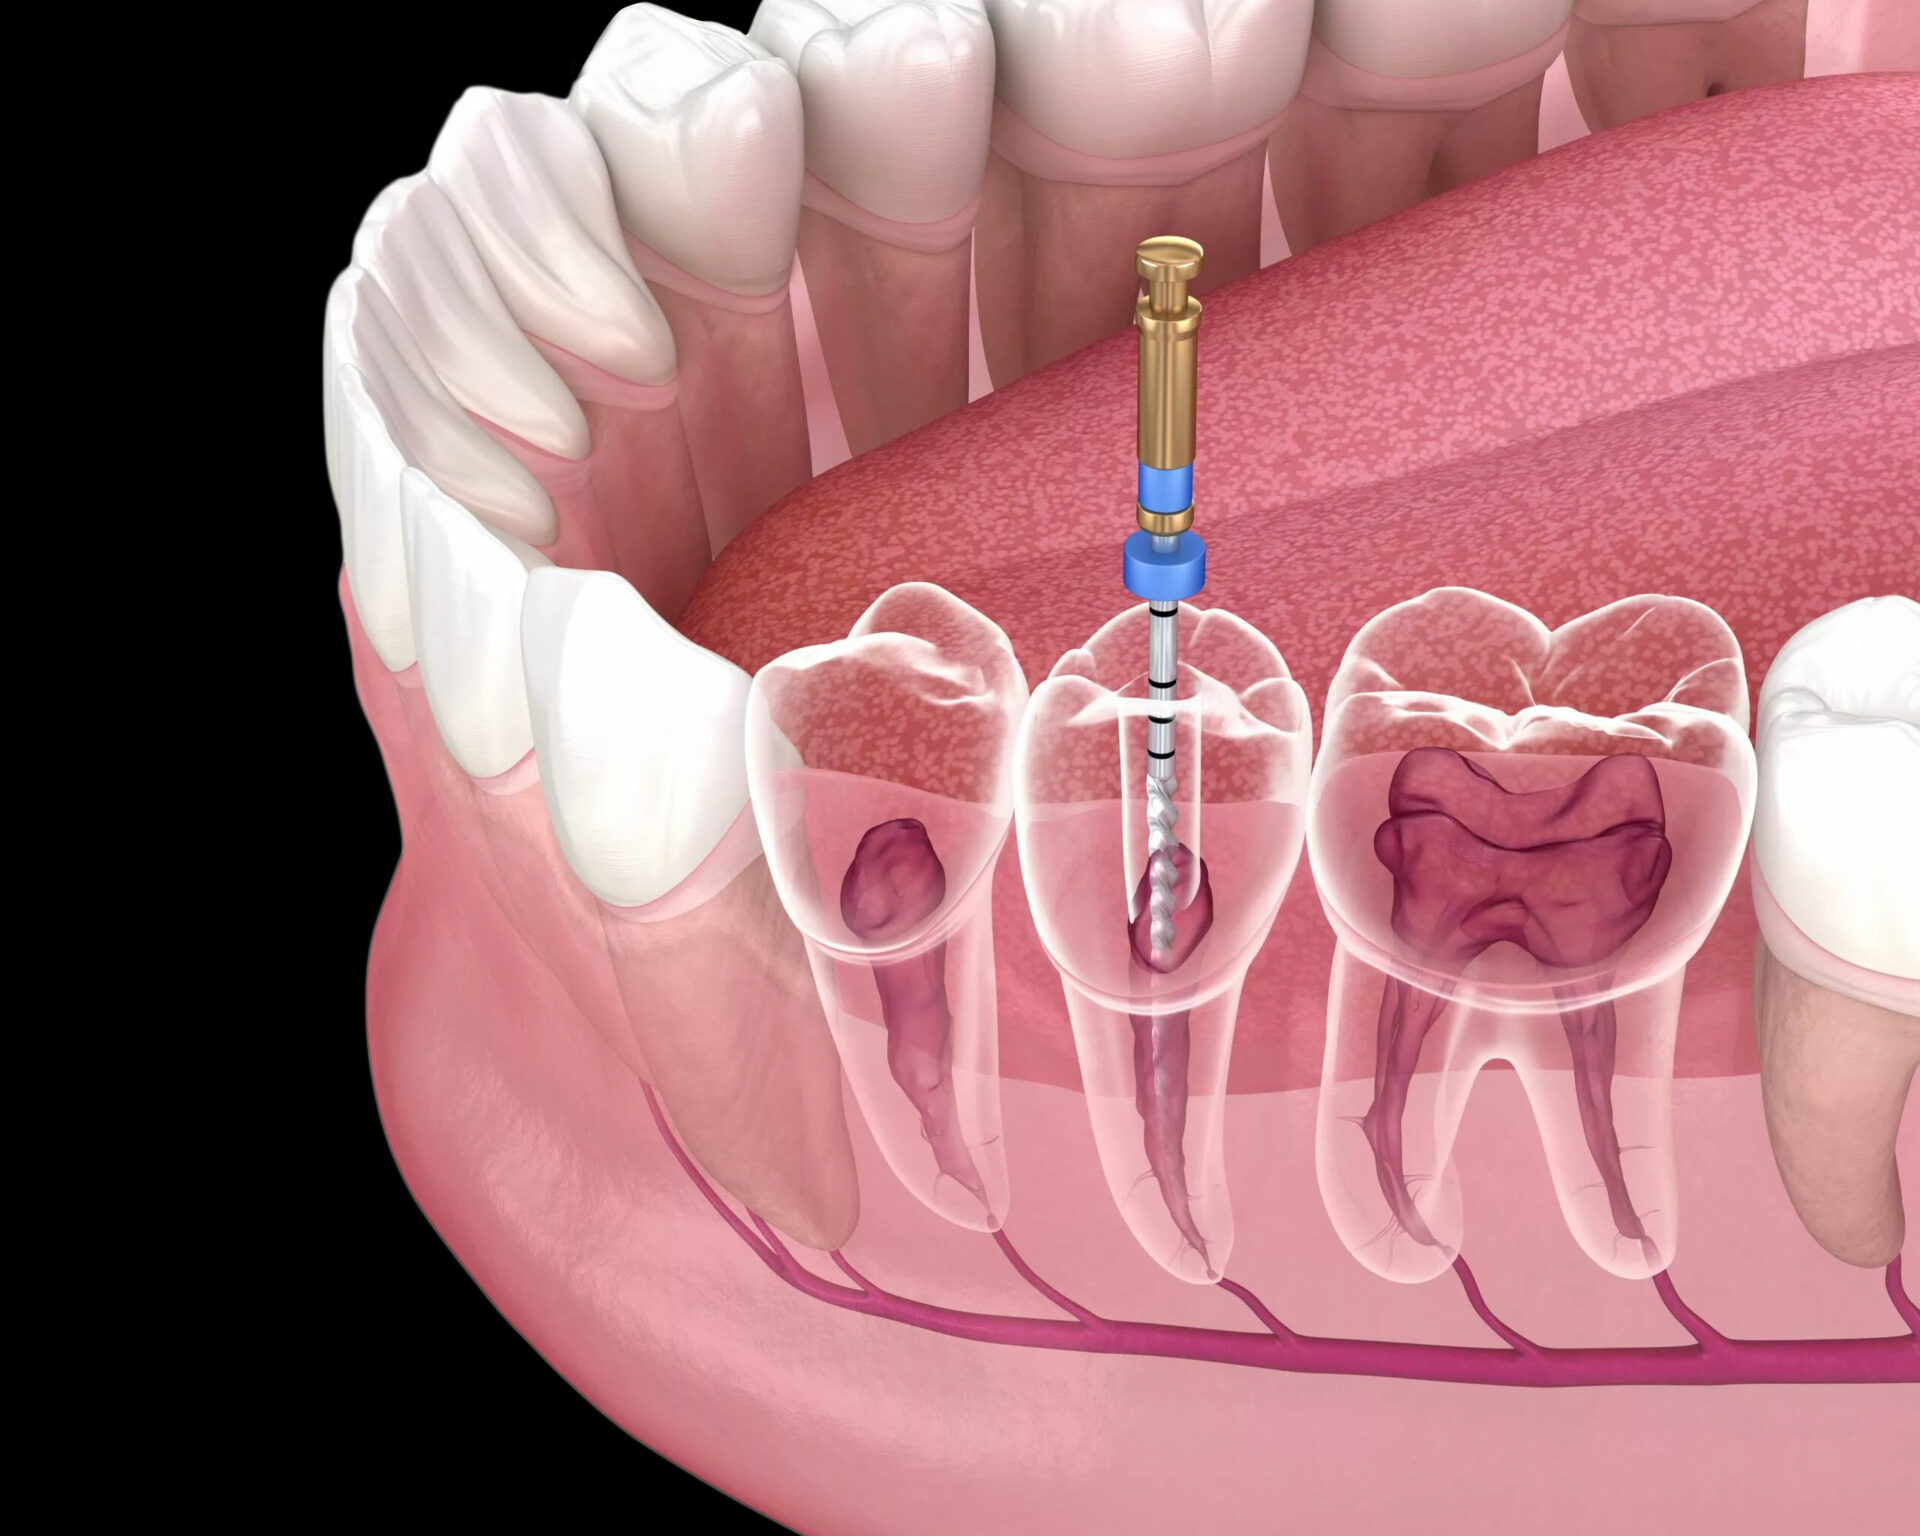

Root canal treatment plays a crucial role in preserving the natural beauty of your smile. When a tooth becomes infected, the priority is not only relieving pain but also maintaining the tooth’s structure—an important element for an aesthetically balanced smile.

After carefully removing the infected tissue, the root canals are shaped, disinfected, and filled with a biocompatible material. This process stabilizes the tooth internally, preventing further damage and allowing it to function naturally again. To complete the treatment, an aesthetically crafted crown is often recommended.

This final restoration enhances both durability and appearance, giving the tooth a natural, harmonious look that blends seamlessly with your surrounding teeth.

By saving your natural tooth, root canal therapy supports facial symmetry, bite alignment, and the overall beauty of your smile—making it an essential component of aesthetic dentistry.